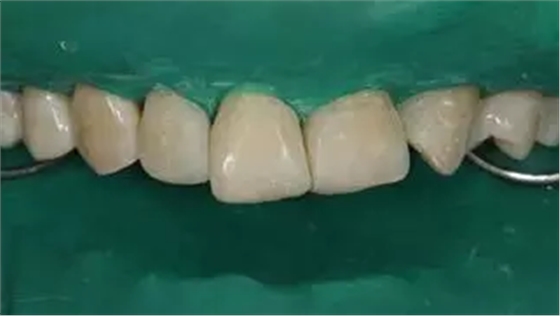

口腔衛(wèi)生尚可,牙齦正常。11,12,21,23 牙體完整,散在間隙,13、24、33、34 頸部楔形缺損,探診無明顯不適,叩(-),無明顯松動(dòng)。冷熱刺激無明顯不適。22 缺失。上下牙咬合穩(wěn)定,覆 覆蓋正常。

術(shù)前上前牙正面照

術(shù)后上前牙正面照